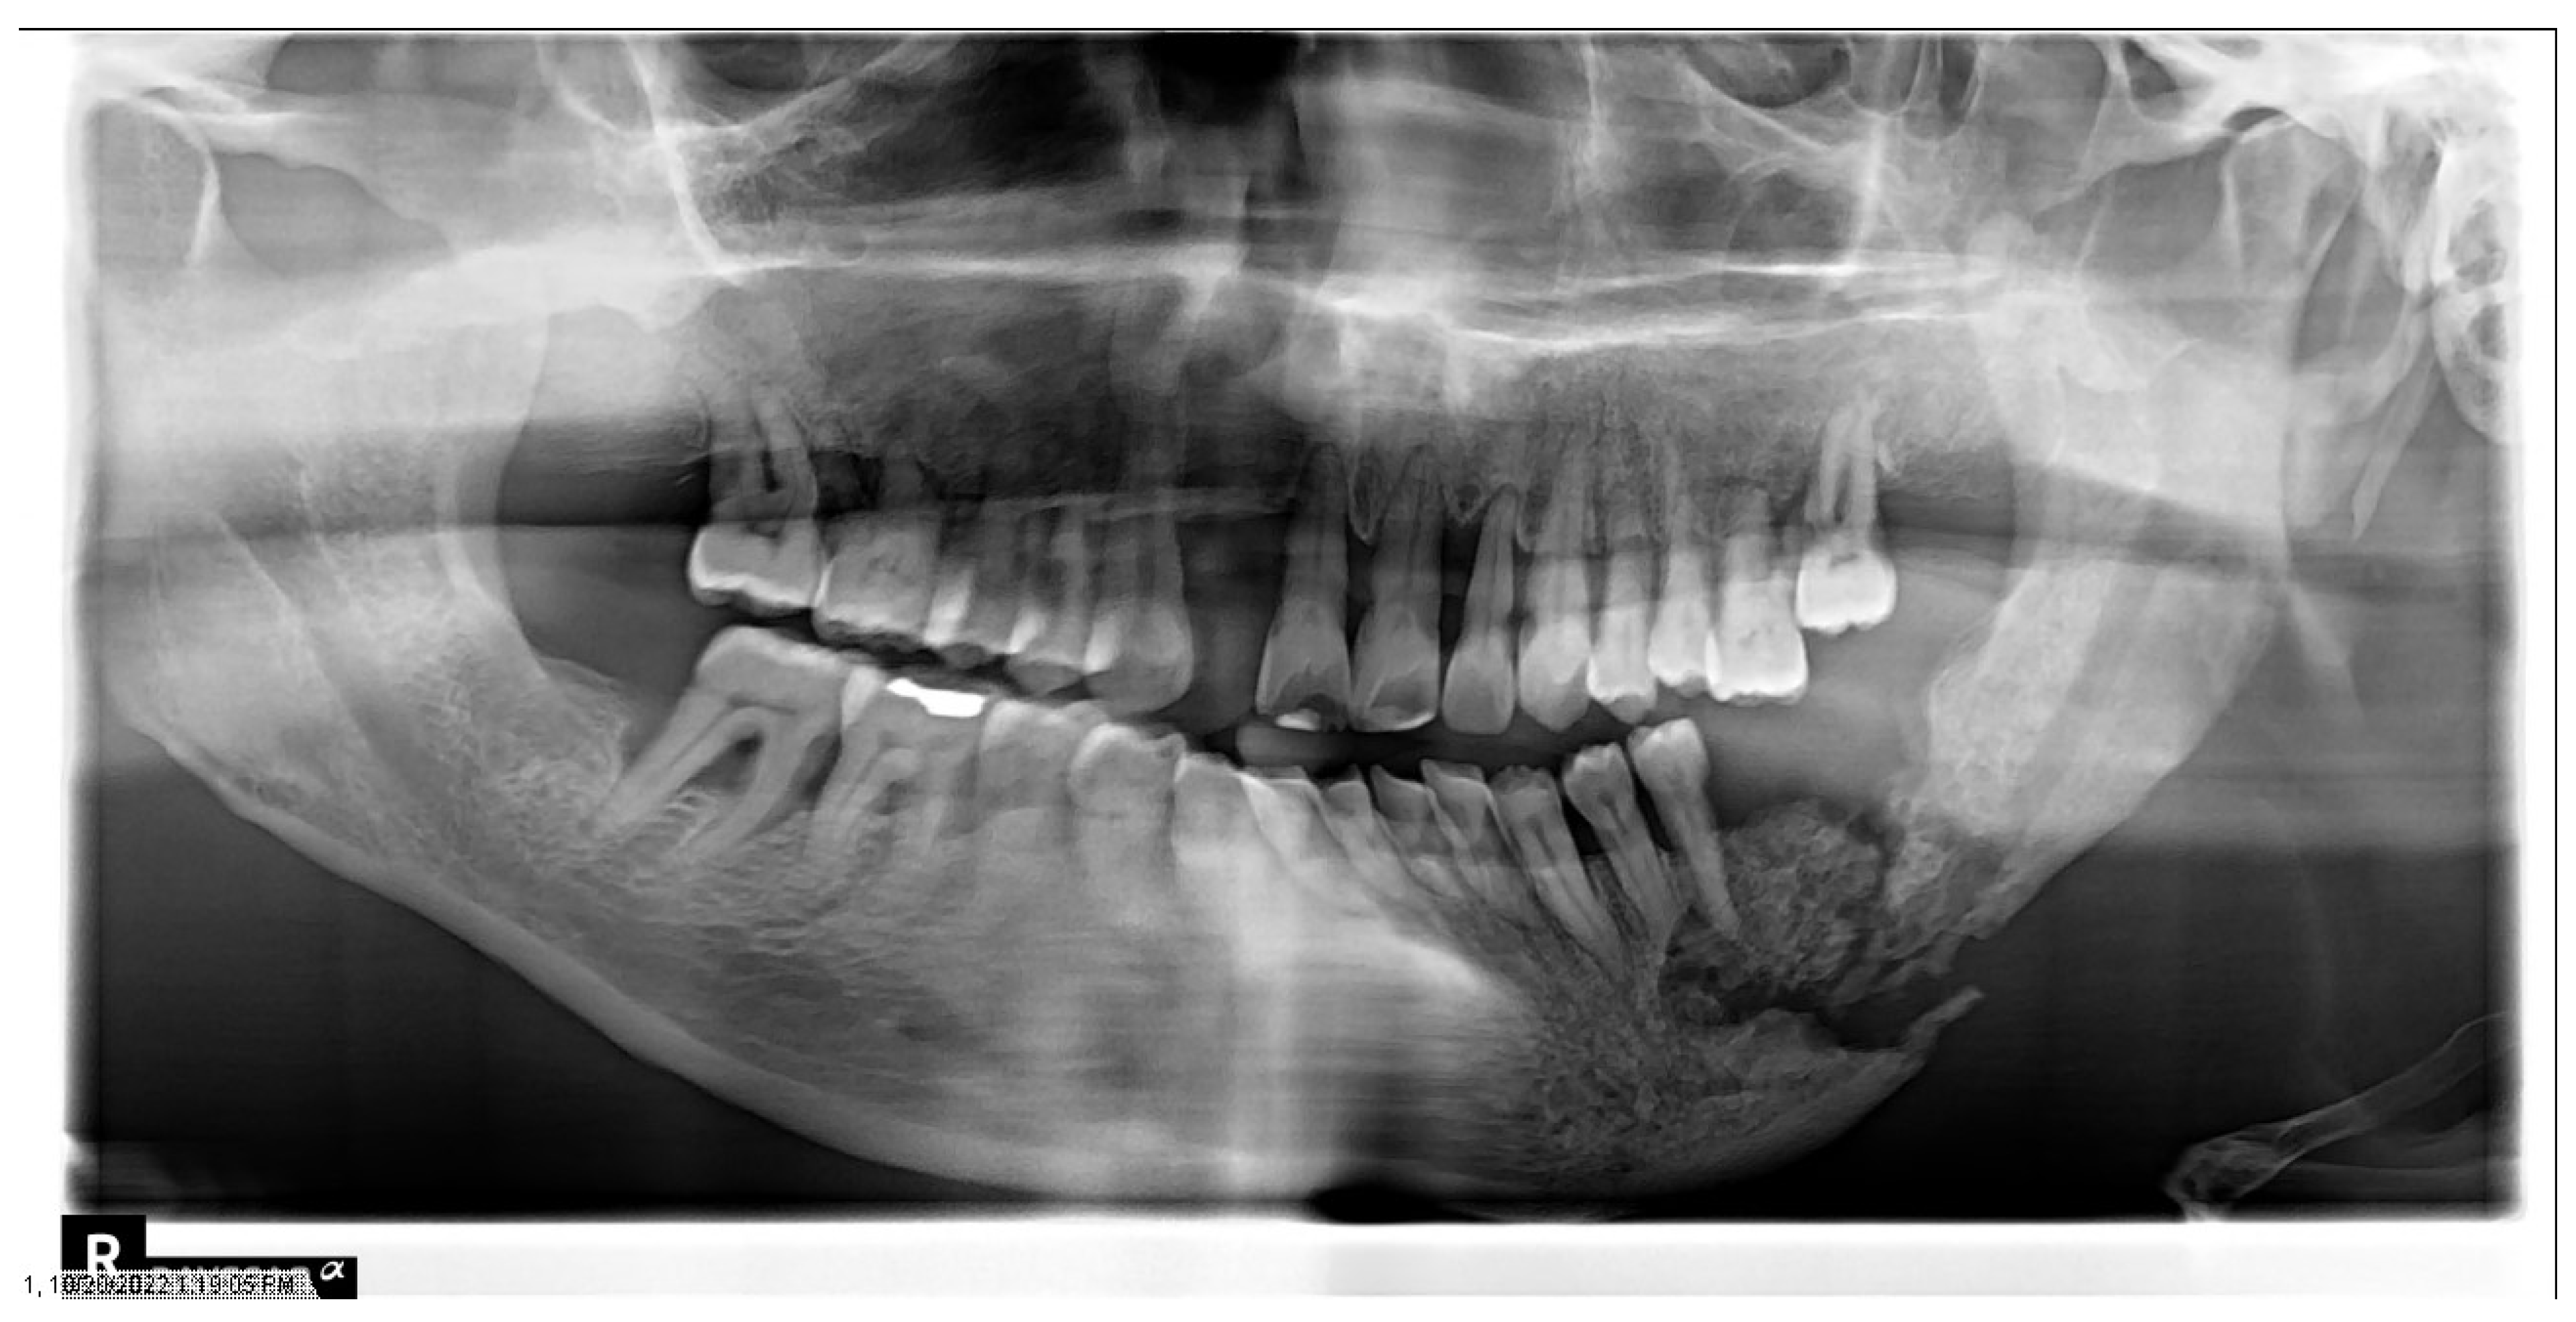

1.4. Osteoradionecrosis

Prevention and Management of Osteoradionecrosis

- Owosho, A.A.; Tsai, C.J.; Lee, R.S.; Freymiller, H.; Kadempour, A.; Varthis, S.; Sax, A.Z.; Rosen, E.B.; Yom, S.K.; Randazzo, J.; et al. The prevalence and risk factors associated with osteoradionecrosis of the jaw in oral and oropharyngeal cancer patients treated with intensity-modulated radiation therapy (IMRT): The Memorial Sloan Kettering Cancer Center experience. Oral Oncol. 2017, 64, 44–51. [Google Scholar] [CrossRef]